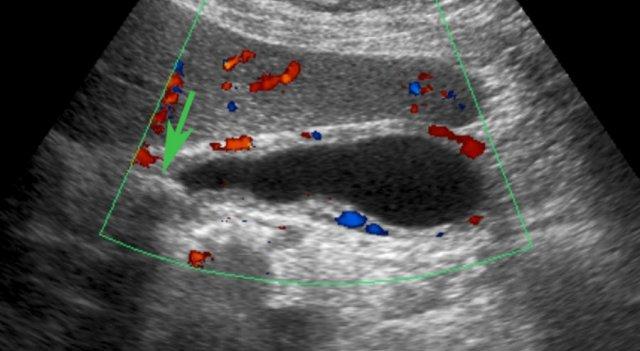

Siêu âm thực hiện 5 giờ sau cơn đau. Có cả phù nề tái tưới máu và tăng sinh mạch thành túi mật. Sỏi gây tắc nghẽn (mũi tên) vẫn còn thấy ở cổ túi mật, nhưng không có phù nề túi mật.

Đôi khi cũng có thể phát hiện tăng sinh mạch thứ phát bằng siêu âm Doppler (hình).